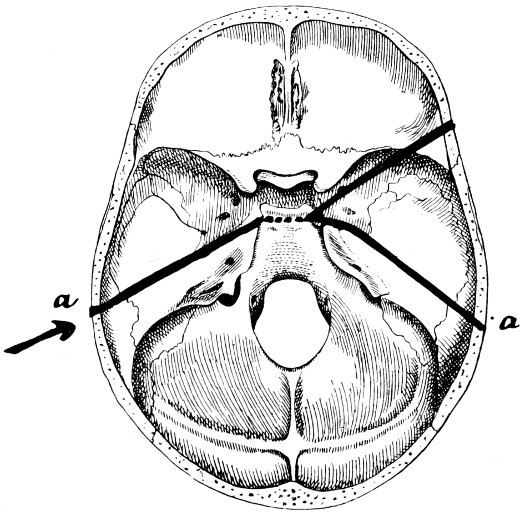

| 28. Illustrating the lines along which forces received on the vault are transmitted to the base | 69 |

| 29 A and B. The base of the skull and the base as seen on transillumination | 70, 71 |

| 30. Plan of the base of the skull | 77 |

| 31. To illustrate the relation of basic fractures to cranial nerves | 81 |

| 32-37. The lines pursued by basic fractures | 83-8 |